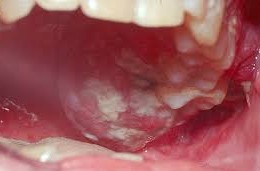

③ 2기

- 특징: 종양의 크기가 2~4cm 사이이며, 여전히 림프절이나 다른 부위로의 전이는 없습니다.

- 증상: 입안의 통증, 이물감, 출혈 등이 나타날 수 있습니다.

- 5년 생존율: 약 70%